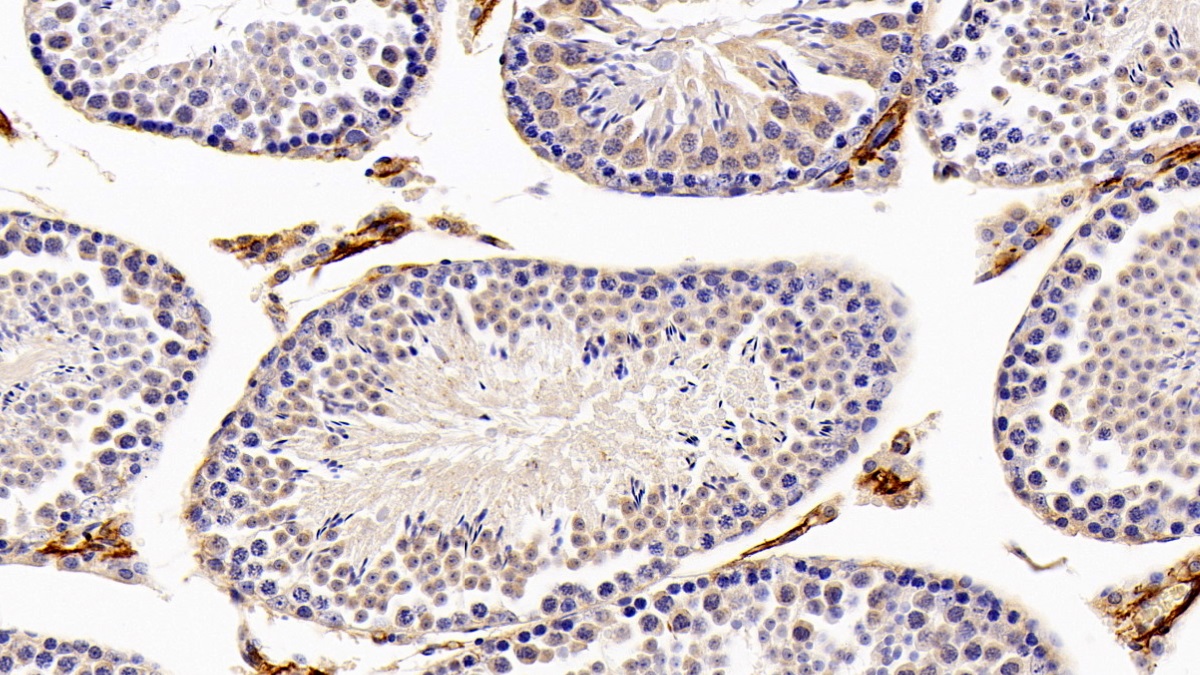

Использование высококачественных первичных антител является неотъемлемым условием получения точных и воспроизводимых результатов в современных научных исследованиях. Например, в рамках онкологического исследования удалось достоверно идентифицировать экспрессию белка PD-L1, что сыграло ключевую роль в оценке потенциальной эффективности иммунотерапии. Применение надежных антител обеспечило стабильность сигнала и высокую специфичность детекции, что позволило получить данные, пригодные для публикации в рецензируемых научных изданиях.

Способы применения первичных антител

Первичные антитела используют в разных методах: от вестерн-блоттинга до иммунофлюоресценции и проточной цитометрии. Всё решает подготовка: нужно грамотно выбрать буфер, точно рассчитать, сколько продукта добавить, и не затянуть с инкубацией. Например, в вестерн-блоттинге без правильной блокировки мембраны фон может всё испортить, а в иммунофлюоресценции фиксация клеток решает, будет ли сигнал ярким. Мы не просто продаём реагенты, а помогаем довести эксперимент до результата: подбираем реагенты и даём советы по методам, если есть специфика в протоколах производителя. Нужен особый подход? Оформите спецзаказ по ссылке — мы найдём решение для вашего проекта.